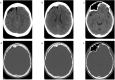

Dyke-Davidoff-Masson syndrome (DDMS) was first described in 1933 as a cerebral condition of hemispheric atrophy characterized clinically by contralateral hemiparesis, facial-asymmetry, seizures, and mental retardation. Neuroimaging findings include asymmetric thickening of the calvarium and enlargement of frontal and ethmoid sinuses. There have been 21 reported cases described in the literature with the syndrome undiagnosed until adult age, likely due to less severe or absent clinical findings or symptoms as described in the case presented in this report. This article describes a case where the Dyke-Davidoff-Masson imaging features were identified as an incidental finding on a CT scan of the brain performed for non-seizure related symptoms. A 54-year-old woman presented with weakness and gait difficulty and only upon further evaluation was she found to have cranial deformities. CT and MRI demonstrate encephalomalacia in the right frontal lobe anteriorly with gliosis and moderate unilateral cerebral atrophy, and extensive hypertrophy of the right frontal calvarium, right ethmoid cells and frontal sinuses.